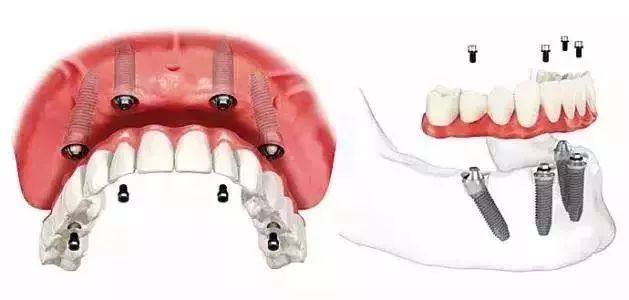

什么是种植牙?

种植牙也叫人工种植牙

包括下部支持种植体、中部修复基台

上部牙冠修复体三部分

通俗地说,就是将与人体组织相容性好

具有一定强度的人工材料植入牙槽

代替缺失的自然牙根

然后在上面戴假牙的一种牙齿修复方法